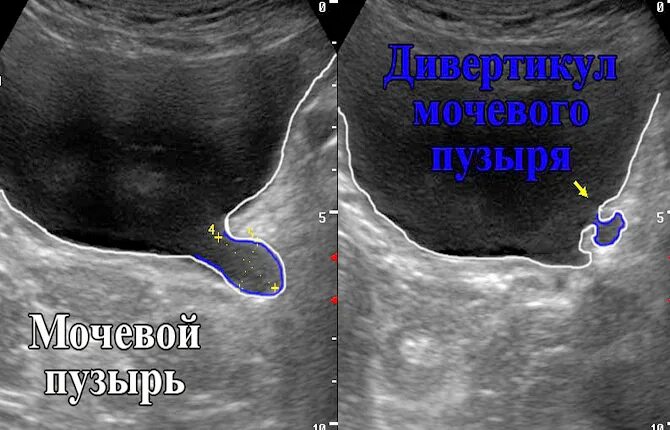

Дивертикул мочевого пузыря что это такое